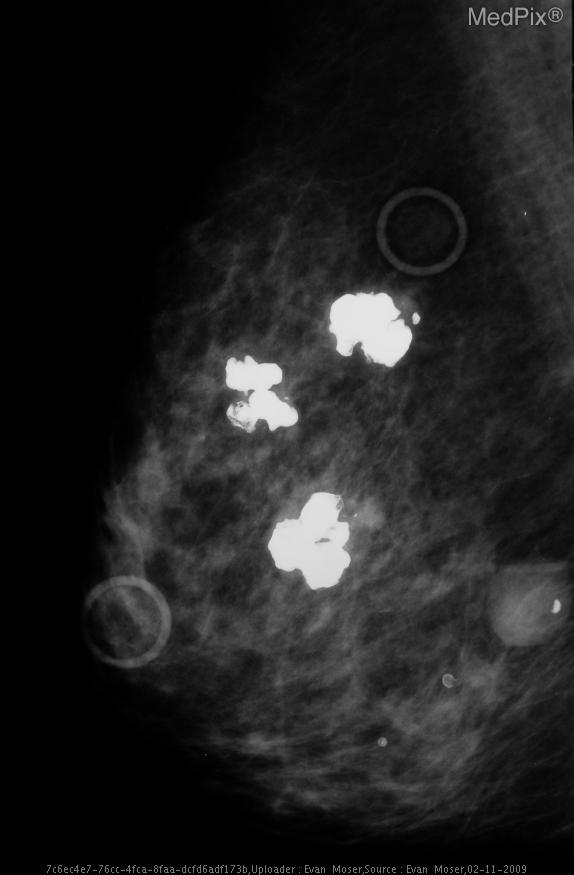

يكشف فحص الماموجرام عن وجود آفة مشبوهة بالسرطان في الثدي الأيسر. لا توجد كتلة واضحة. كيف يمكنك المضي قدما؟

إجابة

الخزعة الأساسية للتوجيه المجسم أو الموجات فوق الصوتية. أو

استئصال خزعة

يقوم أخصائي الأشعة بإجراء عملية توطين الإبرة أولاً.

يتم ضغط الثدي بحامل له إحداثيات على…